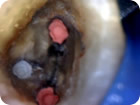

Remoção de Núcleo

Remoção de Núcleo 1

Remoção de Núcleo 2

Remoção de Núcleo 3